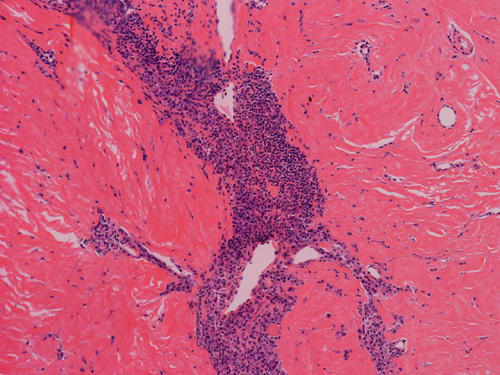

Pathology of the Case: Macroscopically, the nodules are well circumscribed, irregular, and stone hard. The cut surface is solid, gray-white, and free of necrosis. An intraoperative frozen section was performed to rule out metastatic carcinoma, Hodgkin's and non-Hodgkin's lymphoma, and sarcoma. Histologically, the material submitted for frozen section demonstrated hyalinized, hypocellular fibrous tissue with large, calcified nodules (Panel A and B). The section submitted for frozen sections was similar. The bulk of the specimen is composed of hypocellular, hyalinized collagenous tissue with occasional small irregular islands of chronic inflammatory cells (Panel C and D). The nuclei does not display significant nuclear atypia (Panel E). Many large psammoma bodies (Panel F and G)  are present and they are not associated with inflammatory cells. There are also extensive areas with no evidence of either calcifying nodules or inflammatory cells (Panel H). A segment of colon was also resected and the pathology is consistent with Crohn's disease.

Calcifying fibrous tumors are often well circumscribed, firm masses most commonly ranging in size from 1 to 4 cm in greatest dimension. However, the lesions can reach up to 15 cm.  Microscopically, the tumor is a well circumscribed mass showing diffuse hyalinization and benign appearing spindle cells intermixed with a prominent chronic inflammatory infiltrate. The inflammatory component is composed mainly of lymphocytes, eosinophils, and mast cells.  There is usually no hypercellular areas, significant atypia, or mitotic activity. Necrosis and hemorrhage are not seen. This lesion is not infiltrative. As the name implies, a hallmark of the lesion is the presence of calcifications, which may be psammomatous or dystrophic and are sometimes associated with foreign body type giant cell reaction.  It is believed these lesions are reactive because there is no documented evidence of cytogenetic or molecular disruptions that may suggest clonality 8